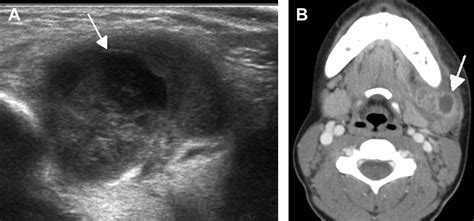

• Imaging Tests: Imaging tests, such as ultrasound, CT scan, or MRI, can help visualize the lymph nodes and detect any abnormalities.